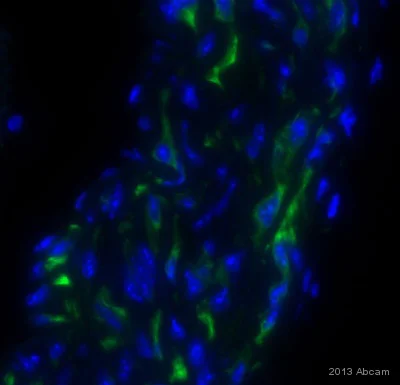

Anti-PACAP antibody GTX37576 from GeneTex | Biocompare.com。Anti-Desmin antibody [Y66] - Low endotoxin, Azide free。Anti-Desmin antibody [Y66] - Low endotoxin, Azide free。7820 INHEEL SLIPON | MUUM。。x1 red strawberryx1 pink strawberryx1 pink tigerx1 seal x1 pig

![Anti-Desmin antibody [Y66] - Low endotoxin, Azide free Anti-Desmin antibody [Y66] - Low endotoxin, Azide free](https://content.abcam.com/products/images/desmin-antibody-y66-low-endotoxin-azide-free-ab216616--immunohistochemistry-formalin-pfa-fixed-paraffin-embedded-sections-img128436.jpg)

![Anti-Desmin antibody [Y66] - Low endotoxin, Azide free Anti-Desmin antibody [Y66] - Low endotoxin, Azide free](https://content.abcam.com/products/images/desmin-antibody-y66-low-endotoxin-azide-free-ab216616--immunohistochemistry-formalin-pfa-fixed-paraffin-embedded-sections-img135003.jpg)